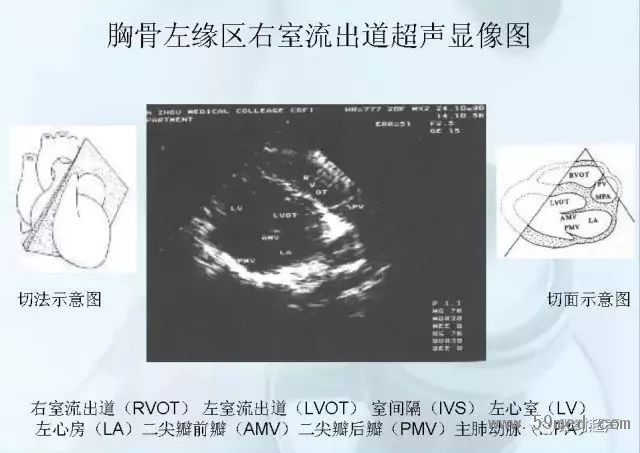

新聞中心 收藏!正常B超解剖圖譜,超實用!